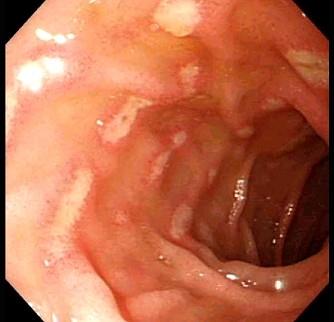

问题 十二指肠溃疡青年病人处理中,下列哪项是正确的 ( )

选项 A、疑有幽门梗阻必须立即手术 B、上述情况均暂不考虑手术 C、服用“胃疡平”片无效,应考虑手术 D、怀疑穿孔必须立即手术 E、大便隐血++,必须立即手术